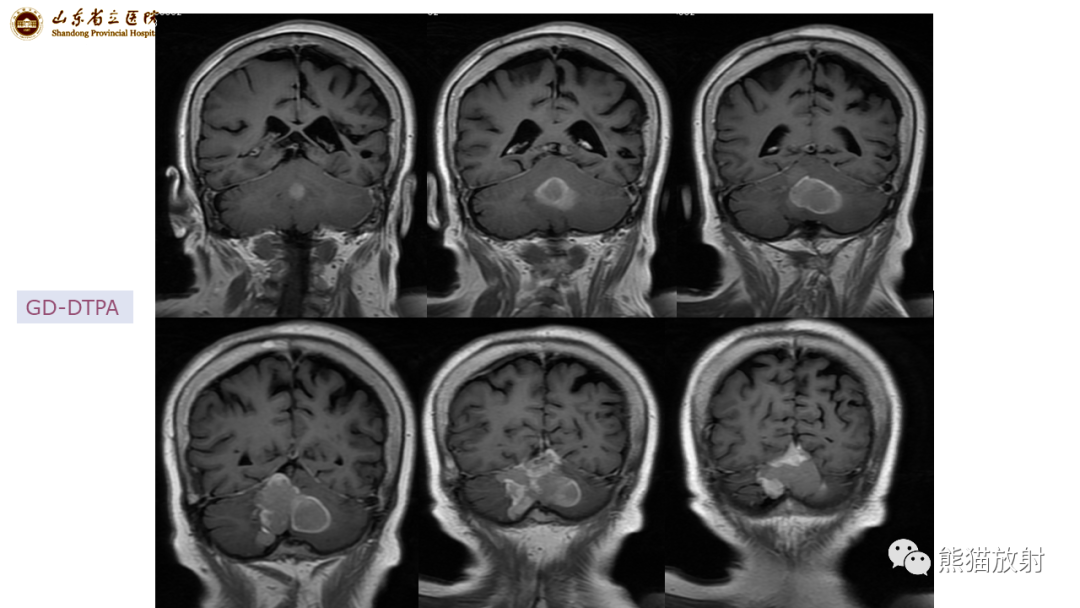

【病例】炎性肉芽肿并脓肿形成 & 成熟性囊性畸胎瘤-2